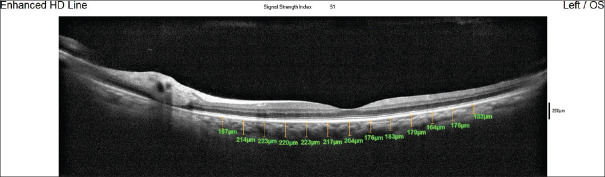

Methods: In this cross-sectional study, 300 eyes of 150 healthy subjects, with no ocular pathology, were scanned in a single session, using a line scan protocol of RTVue XR 100 OCT. Choroidal thickness was measured at the subfoveal region, and six measurements were obtained on either side of the fovea (temporal and nasal) at 500 μm interval apart, up to 3000 μm. The correlation between subfoveal choroidal thickness and age, refractive error, and axial length was assessed.

Results: Three hundred eyes of 150 healthy subjects were included in the analysis. Median age of the study participants was 55 years (interquartile range [IQR]: 44-61). The median subfoveal choroidal thickness was 235 μm (IQR: 210-263). The choroidal thickness was minimum at nasal 3000 μm from the fovea, while it was maximum in the subfoveal region. The point zones which were near the fovea showed thicker choroidal thickness than the outer zones, both nasally and temporally (P < 0.00001 at all locations), and at all point locations the choroid were thicker temporally than nasally (All P < 0.00001). Subfoveal choroidal thickness showed negative correlation with age (coefficient = -0.62, P = 0.03) and axial length (correlation = -8.52, P = 0.02). A decrease in subfoveal choroidal thickness of 0.62 μm/year was found by regression analysis.